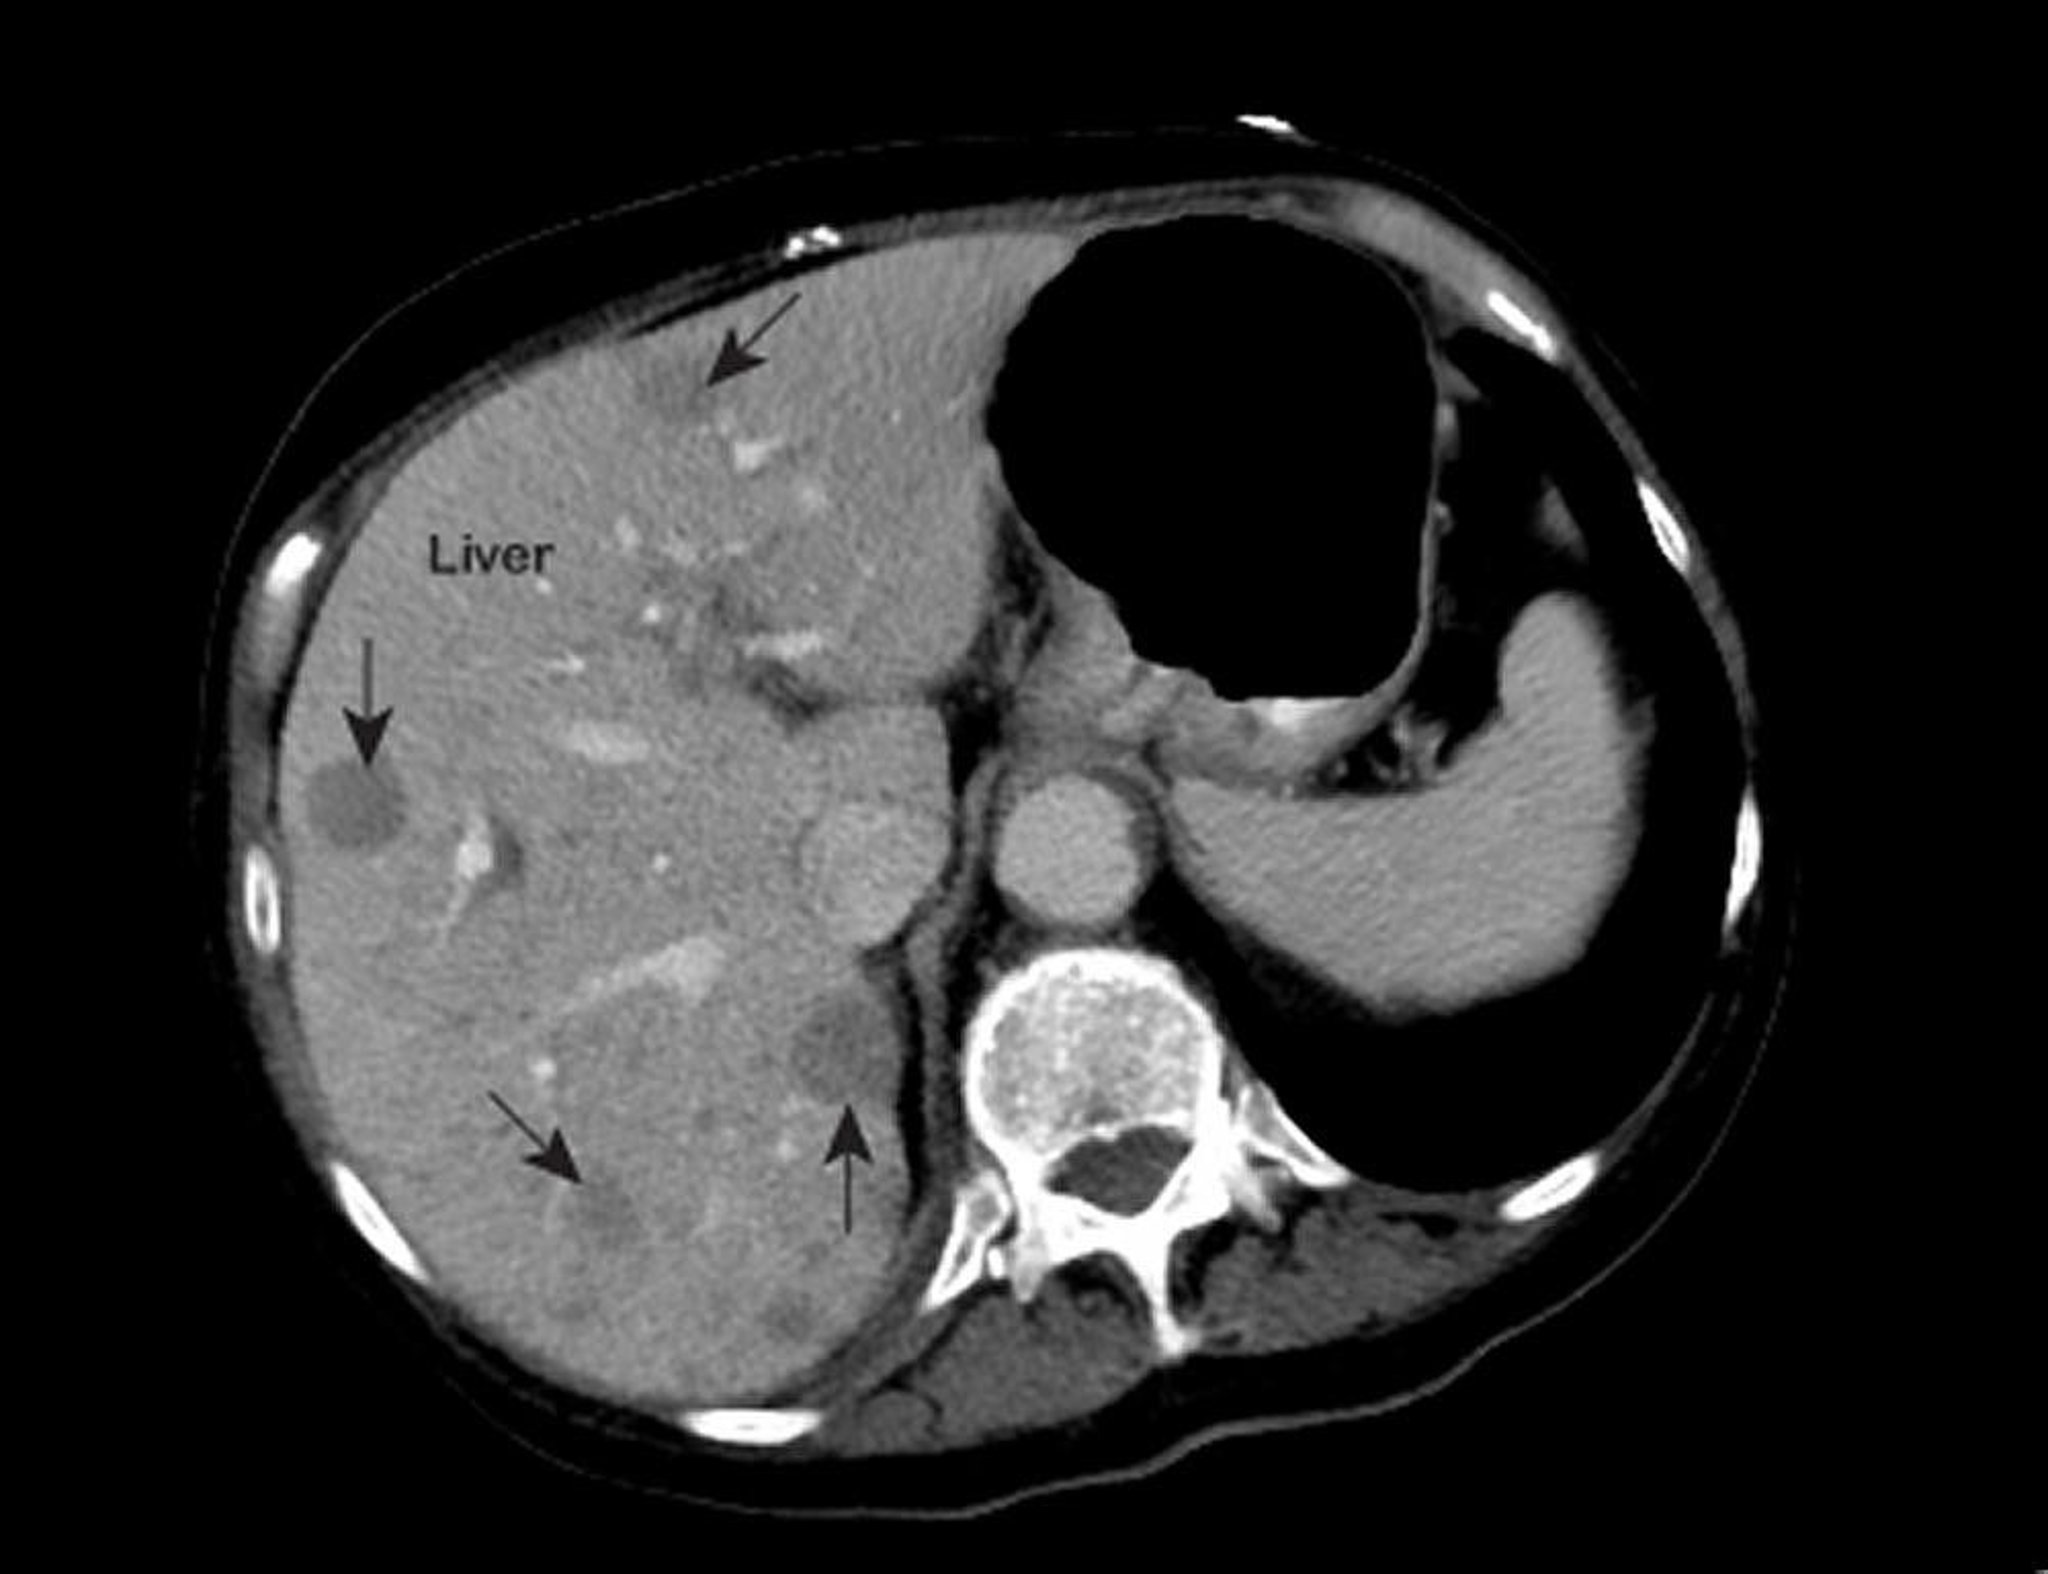

Saratani ya Ini ya Metastatic

An abnormal magnetic resonance image (MRI) of the chest shows abnormal areas (marked with arrows) inside the liver. These findings are typical of metastatic liver cancer.

Photo courtesy of Patrick O’Kane, MD.